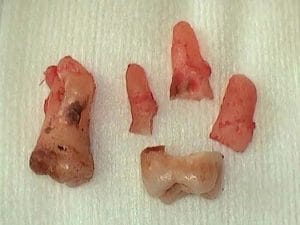

Wisdom Tooth Extraction in Guelph

Tooth extraction is the process of surgically removing a tooth from a patient’s tooth socket. The process is completed within our dental clinic by our qualified dental surgeon.